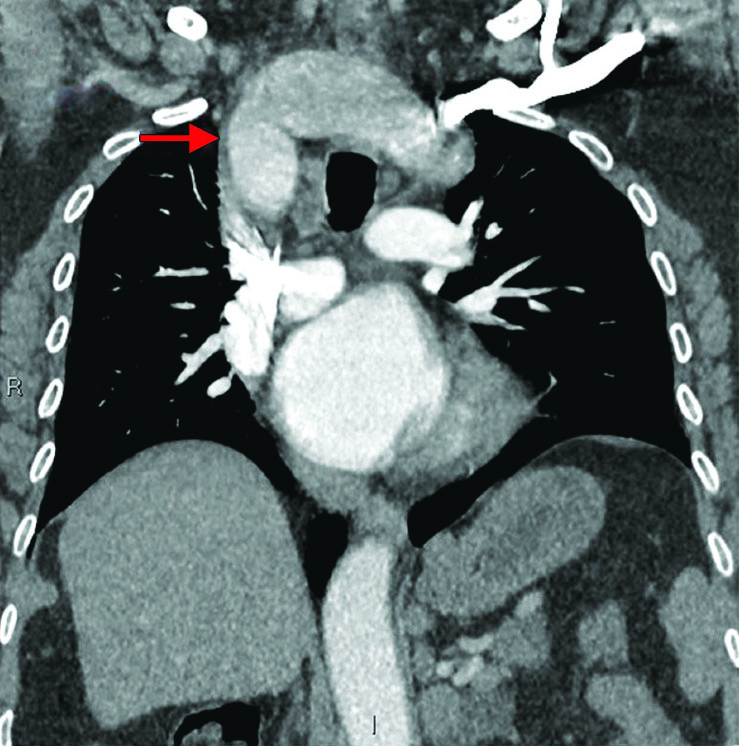

Given the clinical diagnosis of airway obstruction, an urgent CT scan of the neck and chest was performed to identify the cause. That CT demonstrated an anomalous cervical aortic arch. Given the unusual anatomy—transthoracic echocardiography was performed demonstrating a dissection flap in the arch. The aortic valve and ascending aorta were normal (type B Stanford classification). Subsequent CT angiogram (Fig. 1) and 3D CT reconstruction of the arch along with its branches revealed multiple anomalies of the branches (Figs. 2 and 3) and a large type-B dissection of the aorta (Fig. 4). This demonstrated a near-total obstruction of the thoracic inlet with associated compression of the esophagus and trachea (Fig. 5).

Fig. 4: CT aortogram showing dissection